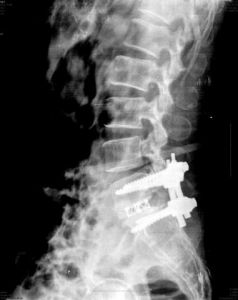

5.一般需要拍攝腰椎正側位、斜位X線片

有時需加攝過伸過屈側位片。可見椎間隙狹窄、骨質增生、椎小關節骨性關節炎改變等,多見於腰4-5與腰5骶1之間。

6.CT檢查

可見矢狀徑小於12mm,有向後延伸的骨刺等,一般取腰4-5,腰5-骶1的小關節水平攝CT片。

2.手術治療

手術治療主要適用於:經非手術治療無效者;出現明顯的神經根症狀;對於繼發性腰椎椎管狹窄,進行性加重的腰椎滑脫及伴有腰椎側凸或後凸者,已伴有相應的臨床症狀和體徵。

(1)減壓的病例可以採用傳統常規治療方式包括椎板開窗、半椎板切除、全椎板切除等,也可以採用微創技術治療。

(2)對於需要“減壓+固定”病例可以採用傳統常規治療方式,也可以採用微創技術治療。而融合技術可以選用橫突間後外側融合技術、椎板間後側融合技術、椎間融合技術等。